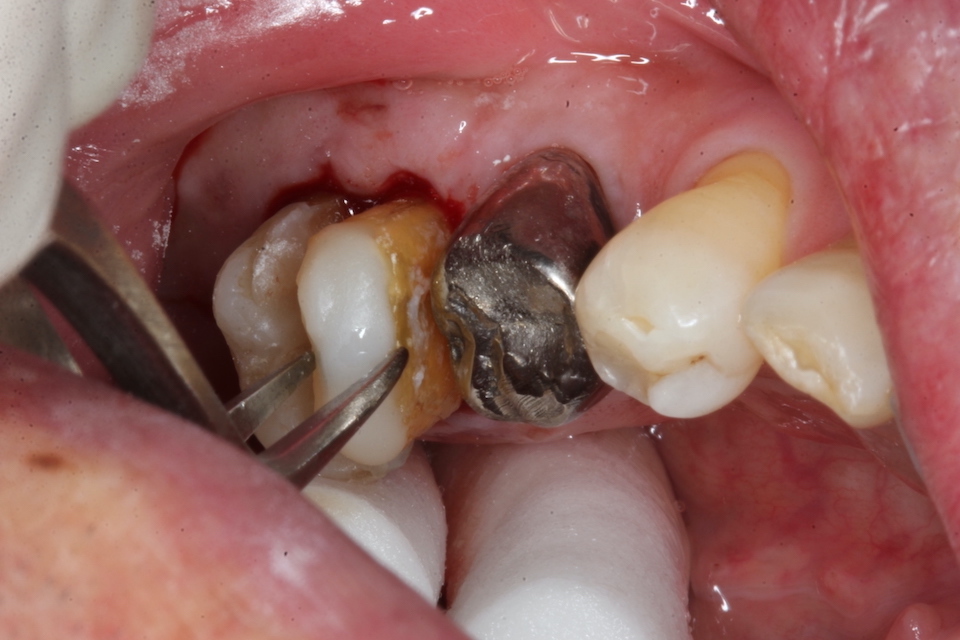

70代男性、左下7、歯根破折、自発痛++

今日は破折した歯根の接着面を新鮮面を出しきれいにしてスーパーボンドの筆積み法で貼り合わせポストを入れてCR併用で再建し、抜歯窩に挿入固定するだけだ。

以下時系列でどうぞ

根管充填材と歯質との間には隙間が存在し、細菌の代謝産物の黒色物質のFeSで覆われている。緊密な充填など絵に描いた餅にすぎない。

遠心根の切断面もスーパーボンド+CRで覆っておく